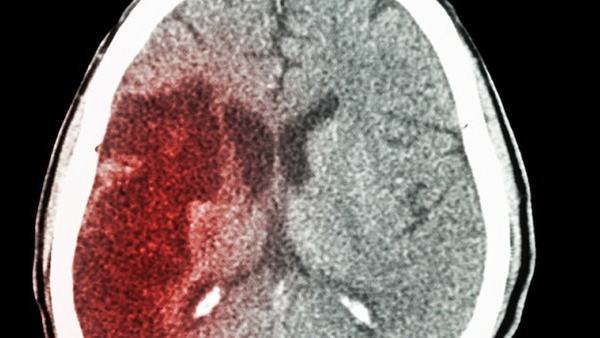

最后,早期诊断和治疗对于小脑萎缩的治疗效果也至关重要。一旦发现中风的症状,患者应立即就医进行详细检查。根据疾病的特点和患者的情况,医生可以制定个性化的治疗方案,旨在最大限度地减少疾病的进展,促进患者尽可能长时间地保持独立生活能力。